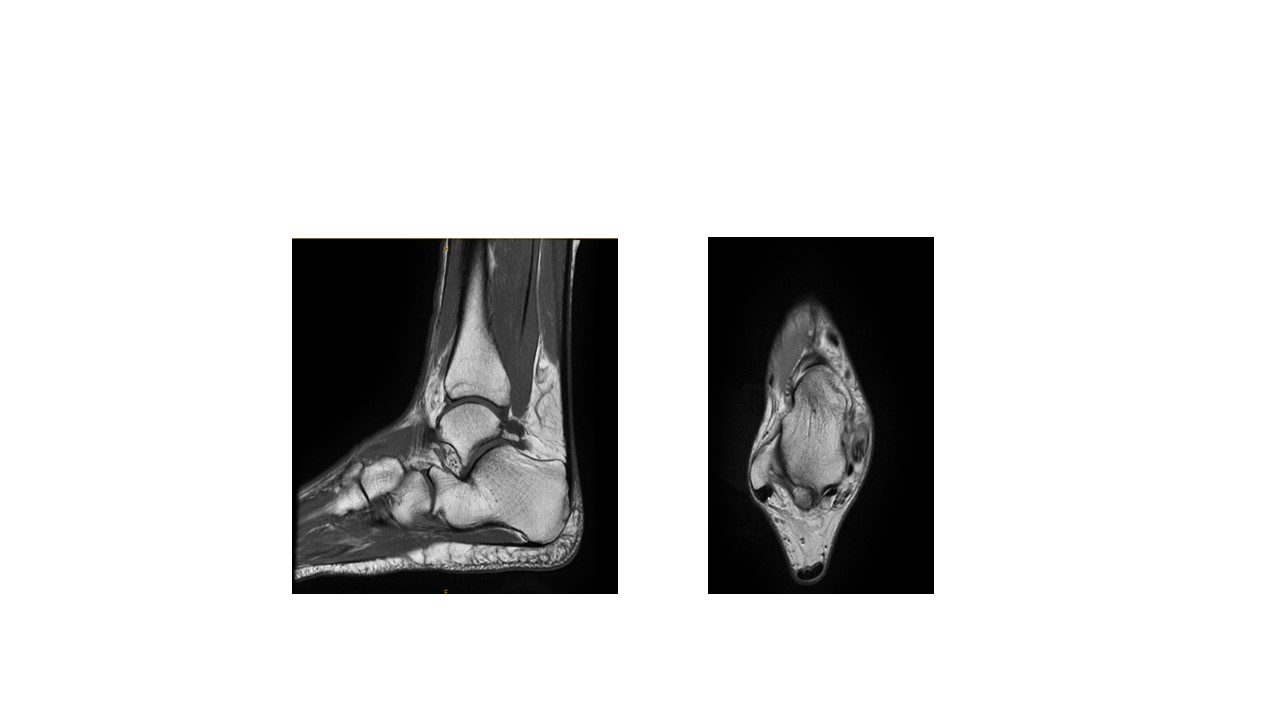

These MRI scans are “weighted” towards bone and show with excellent detail the Os-trigonum at the back of the ankle joint. A fluid-sensitive MRI sequence is reviewed alongside these images to determine whether there are signs of inflammation such as fluid surrounding the Os-trigonum of FHL tendon